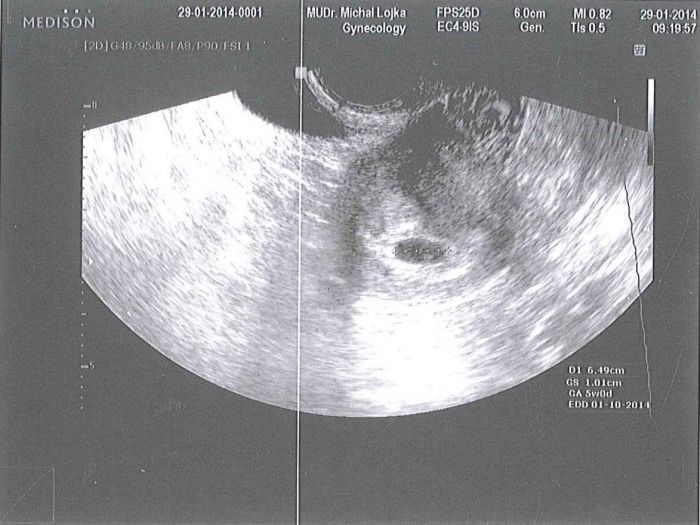

[439051] No uvidím...asi to počítají jinak... já byla hned zvědavá..ale tak hlavně že je tam kde má být... a aby hezky rostlo a vyvíjelo se jak má... dovolil aby můj skoromanžel se šel podívat na ultrazvuk i když dělal vnitřní. už teď se těším na 14.2.

pěkný obrázek

ladybird krasna fotecka, muj chlap by vnitrni uz nedal.. je to zarlivec